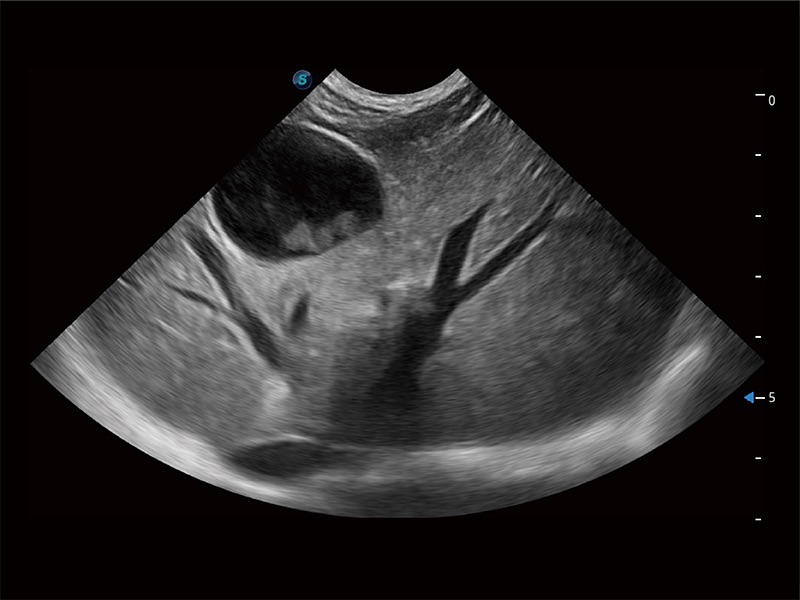

ProPet 80 配備了豐富的心臟探頭群、先進(jìn)的成像技術(shù)和專業(yè)的心臟測量工具,可幫助動物醫(yī)生為不同體型和生理結(jié)構(gòu)的動物提供心臟和心肌功能的全面評估。

高性能和先進(jìn)的臨床應(yīng)用工具可以為動物醫(yī)生提供臨床信心。ProPet 80 搭載了先進(jìn)的腹部和淺表應(yīng)用工具,幫助醫(yī)生在日常臨床實(shí)踐中發(fā)揮前所未有的作用。